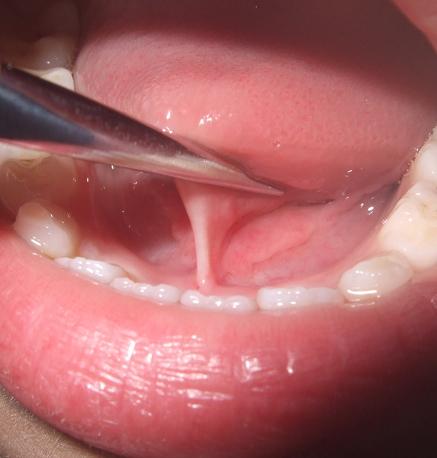

舌头下面正中的“筋”就是舌系带

张大嘴上抬舌头,可以看到舌头下面正中连着的一根“筋”,这便是舌系带。

我们所谓的舌系带过短指的是舌系带与舌腹以及口底的附丽点过于靠前,使得舌体的上抬、前伸以及左右摆动活动受到限制。

- 舌系带过短导致舌头不能正常伸出口外,勉强伸舌时,舌尖会出现由于舌系带牵拉导致的凹陷;